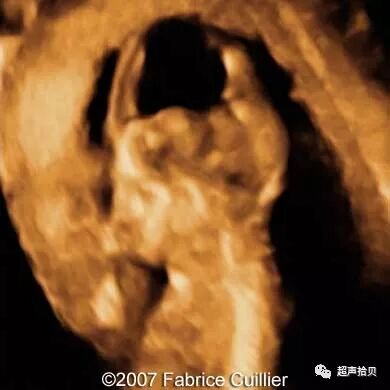

图3胎儿在妊娠25周时从表面到颅骨的三维图像。 A和B,胎儿的表面部分和面部图像。 C和D,胎儿脑部更深的三维切片。 E和F,三维切片显示胎儿脑中的蛛网膜囊肿(箭头)

图4:妊娠26周时的产前MRI:第三脑室蛛网膜囊肿的横向(A),矢状(B)和冠状面(C)平面引起脑室扩张